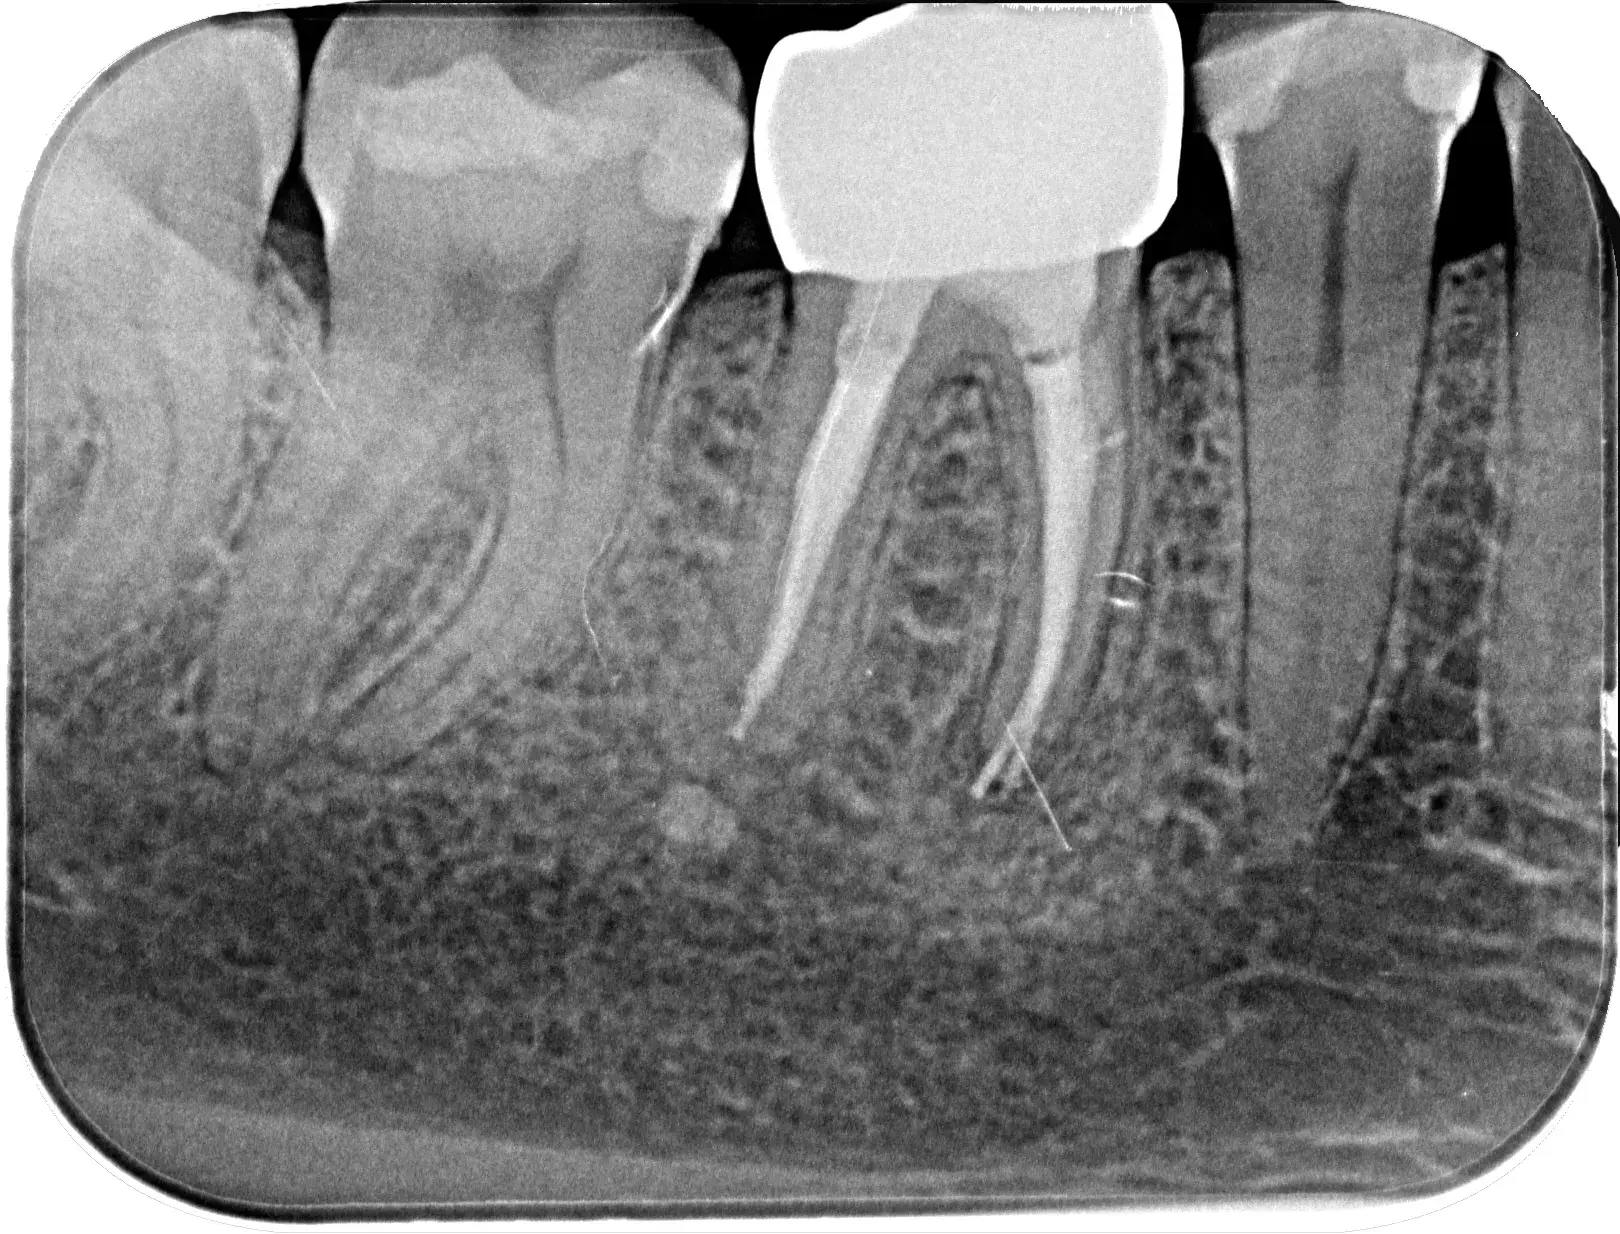

In diesem Fall mussten wir eine mangelhafte Fremdbehandlung korrigieren: Ein im Kanal abgebrochenes Instrument des Vorbehandlers blockierte den Weg und löste eine Entzündung aus. Durch präzises Bypassing konnten wir das Fragment sicher umgehen und bergen, um den Zahn bis zur Wurzelspitze erfolgreich zu retten.